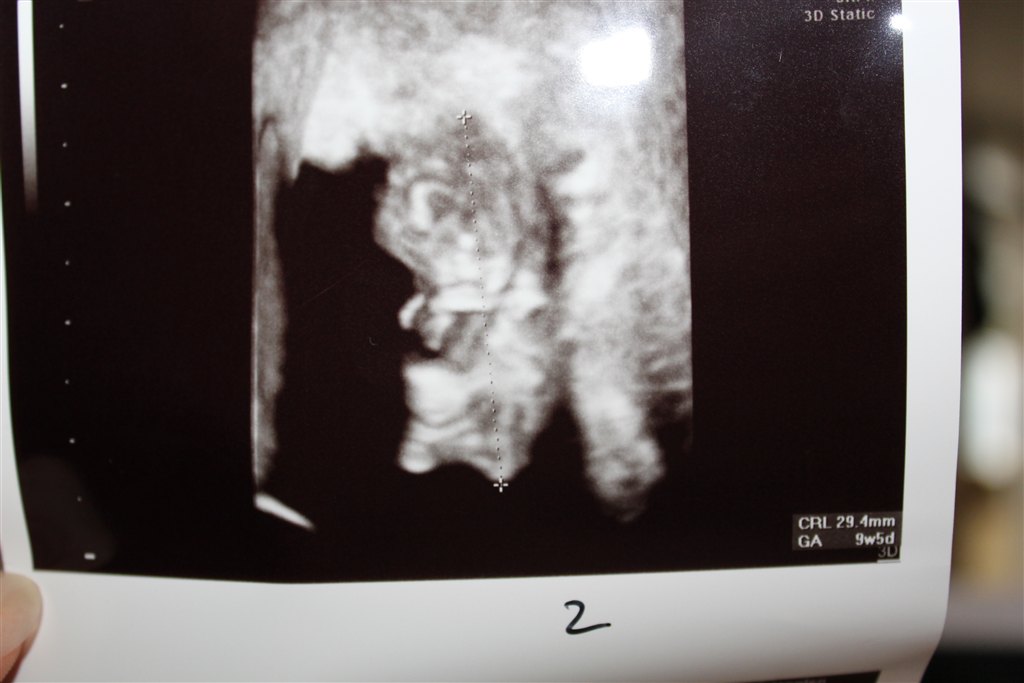

Her er lidt billeder fra scanningen af tvillingerne i dag De havde det fint, men den ene tvilling var lidt mindre end den anden, så der skal lige holdes lidt opsyn med den for at se, om den vokser som den skal

Vedhæftede fotos (klik for at se i fuld størrelse)